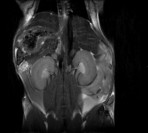

Small Animal Multimodal Imaging

Magnetic Resonance